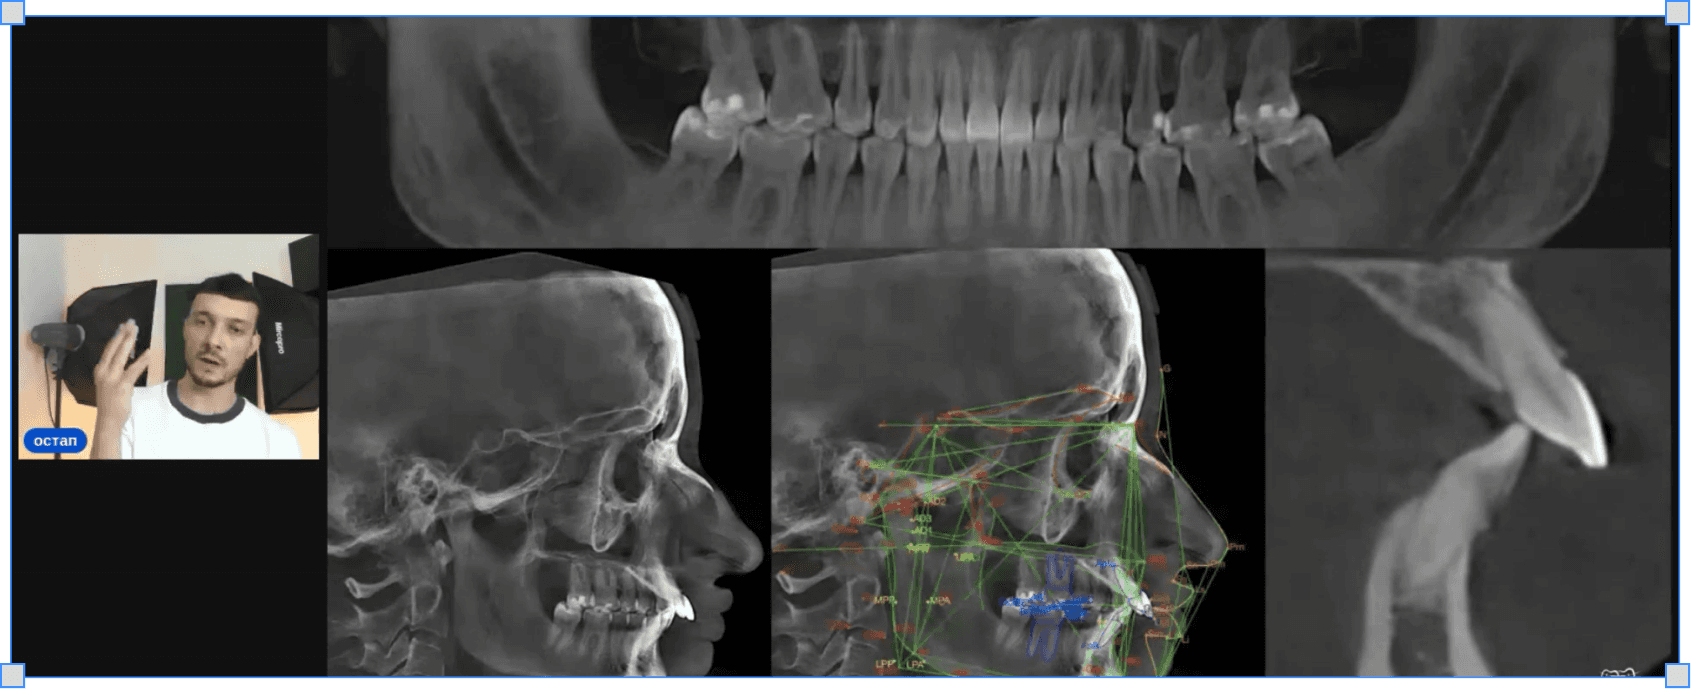

Як діагностувати другий клас для видалення

Фотографії, аналіз скученості і трем — що дивитись і в якому порядку до будь-якого рішення

Як визначити таймінг і вибір видалення

Коли видаляти, коли чекати і що змінюється залежно від стану кістки

Як асиметрично видаляти премоляри верхнього ряду

Логіка вибору — четвірка чи п'ятірка, з якого боку і чому це не завжди симетрично